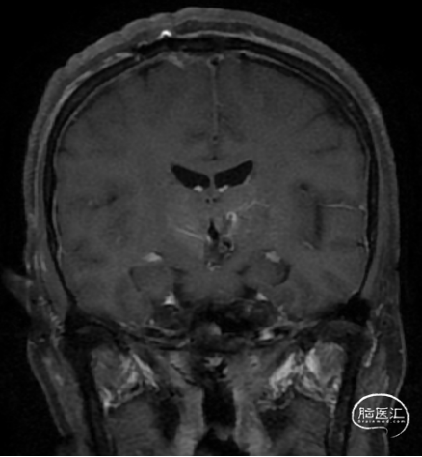

术前诊断:中脑及脑桥左份、左侧基底节区占位:海绵状血管瘤可能。

术后MRI